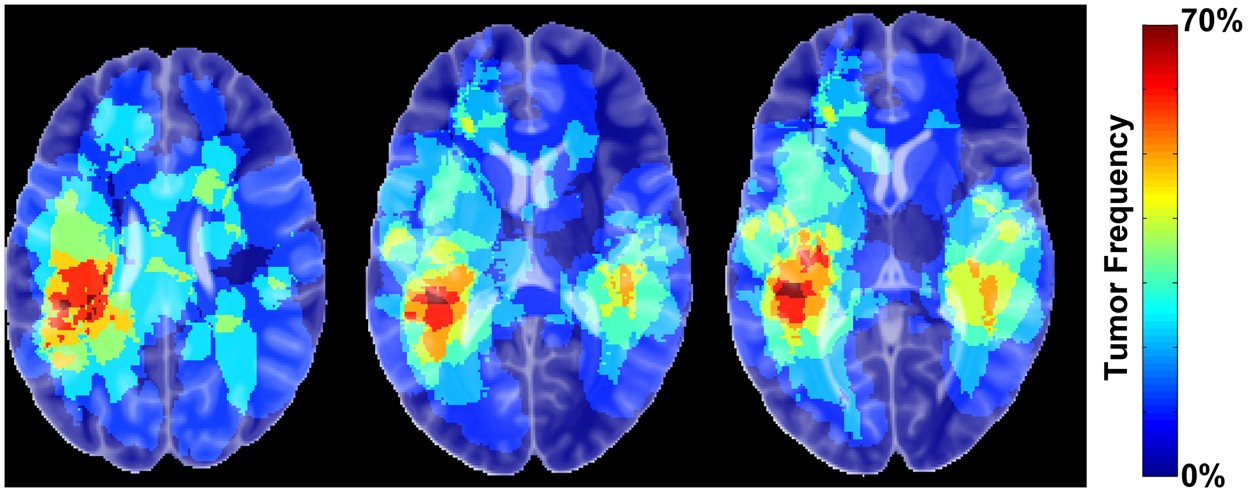

The frequency of tumour occurrence. Three axial slices are illustrated, indicating a predominance tumour occurrence within the temporal lobes.